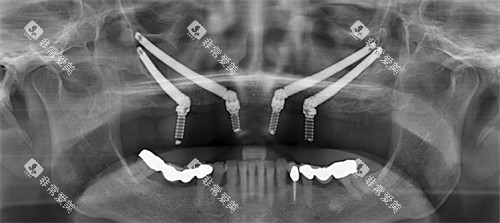

门诊部的特色项目众多,其中穿颧穿翼种植牙技术是一大亮点。

穿颧穿翼种植牙适用于一些骨量重度不足的患者,无需大量植骨就能完成种植,大大缩短了治疗周期,减轻了患者的痛苦。

同时,上颌窦植骨术、神经避让术、狭窄骨头种植手术等也是该门诊部的特色项目,展现了其在复杂口腔种植领域的可靠实力。

技术优势:门诊部拥有较高的种植牙技术,如前面提到的穿颧穿翼、即刻种植等。